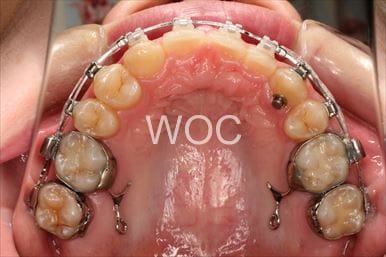

治療中1

- 年齢:20歳女性

- 主訴:出っ歯が気になる

- 基本矯正料金:120万円

- 治療期間:1年7ヶ月

- 抜歯部位:上顎両側第一小臼歯